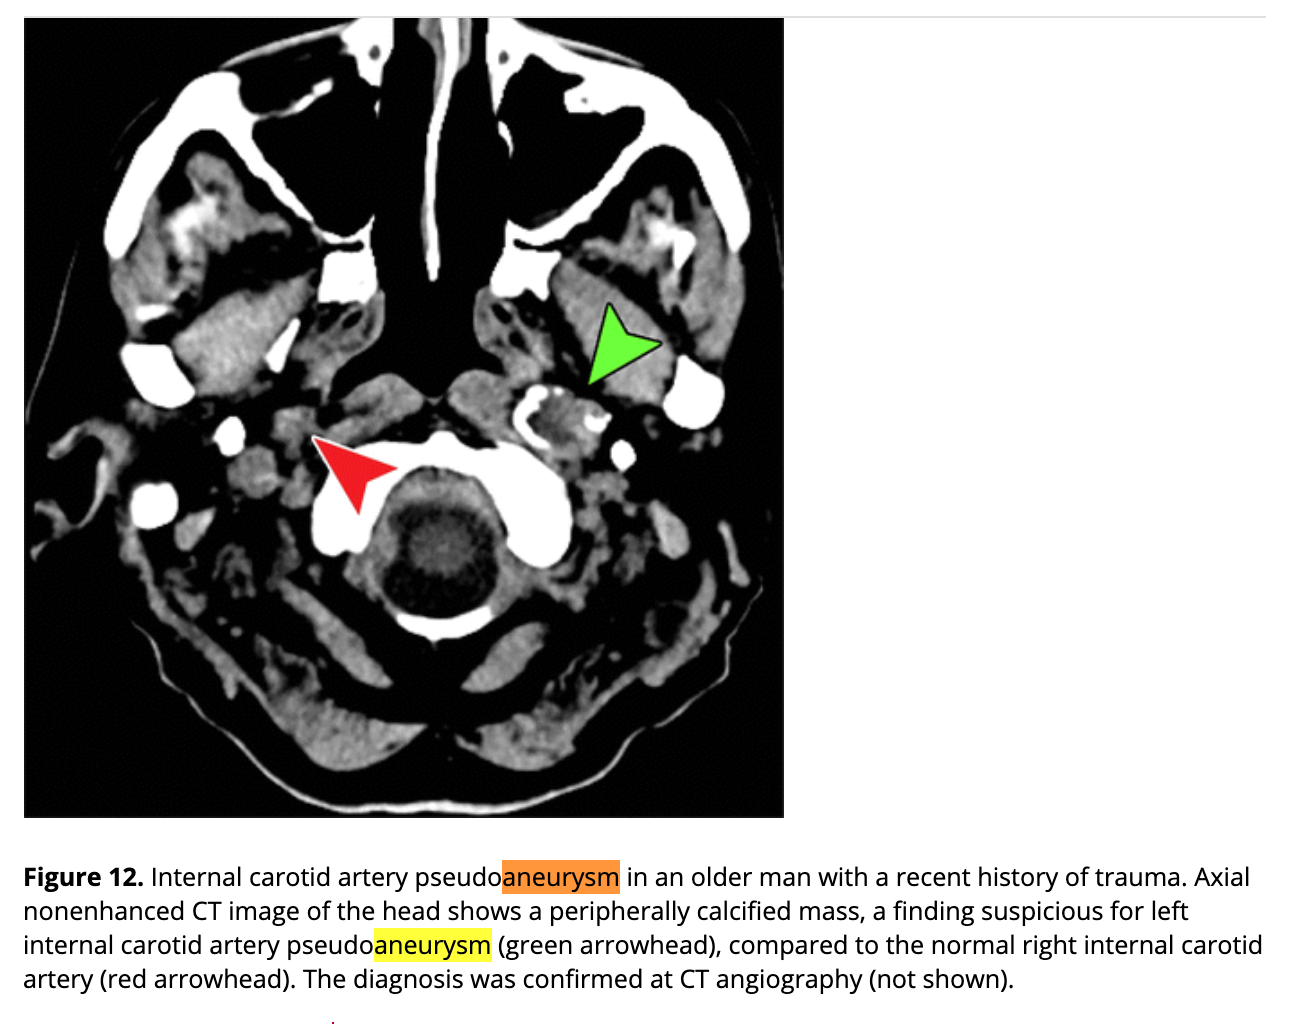

Central skull base Aneurysms